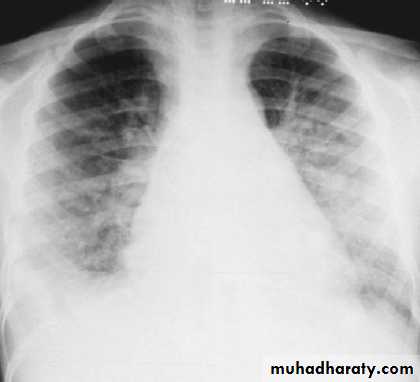

Respiratory distress, orthopnea, and cough may be symptoms of pulmonary edema and heart failure.

CXR is indicated in those with signs of heart failure or respiratory distress.

CXR of a patient with poststreptococcal glomerulonephritis showing pulmonary edema